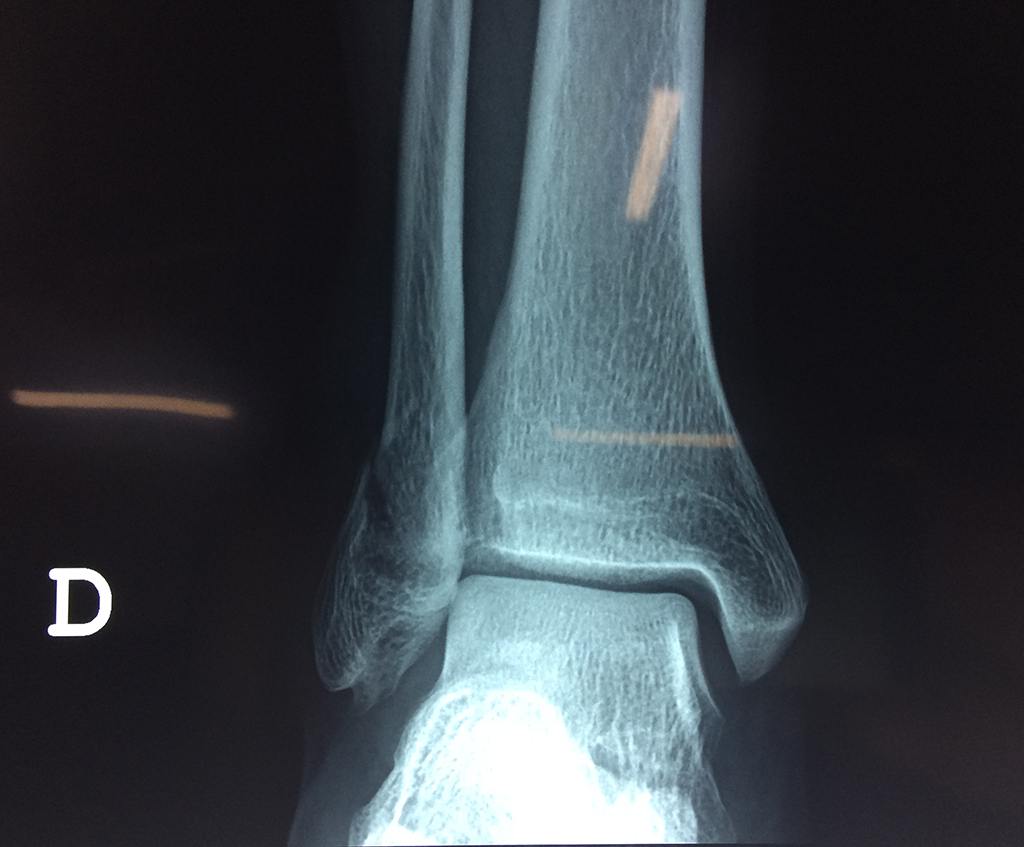

Una fractura de tobillo es la rotura de uno o más de los huesos del tobillo. Estas fracturas pueden ser:

- Parciales (el hueso está sólo parcialmente fisurado, no del todo).

- Completas (el hueso está perforado y está en 2 partes).

- Producirse en uno o ambos lados del tobillo.